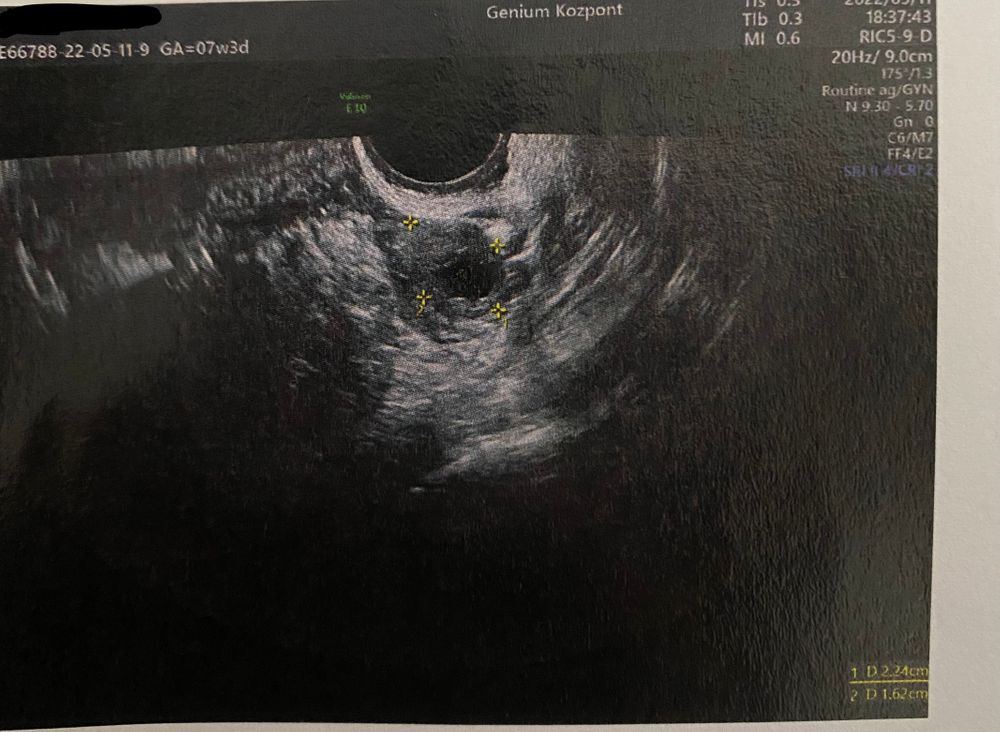

Желтое тело ?!

Изображение

Это ведь желтое тело ?! А где посмотреть какого оно размера ?! В «описание» написано 22*16 мм но на венгерском … а я вообще венгерский не понимаю 🫤🙄 может там написа